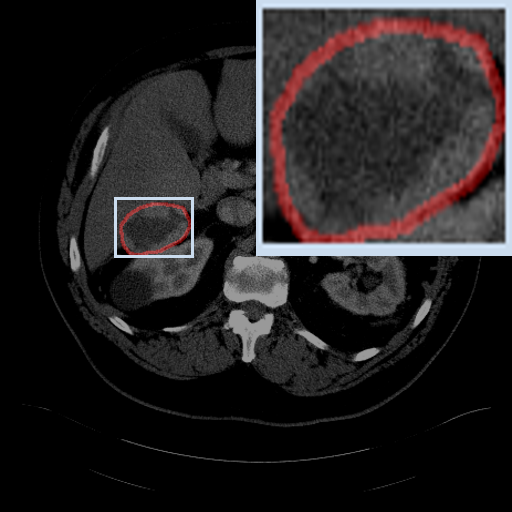

Figure 3: Qualitative comparison visualization of DEAP-3DSAM and baselines on four datasets.

IV-B2 Qualitative Performance Comparison

We also performed qualitative analysis on four datasets. As illustrated in Fig. 3, DEAP-3DSAM accurately identifies the target regions and closely matches their size. In contrast, 3DSAM-Adapter [3dsamadapter] exhibits limitations in matching the size and shape of the target regions. This proves that DEAP-3DSAM captures more complex image features, owing to its Dual Attention Prompter and Feature Enhanced Decoder. Furthermore, while these SAM-based methods are nearly capable of localizing the target regions, many traditional methods, i.e. UNETR++ [unetr++], Swin-UNETR [swinunetr], and TransBTS [transbts], struggle to achieve this. This highlights the potential of SAM-based methods for addressing complex 3D segmentation tasks.